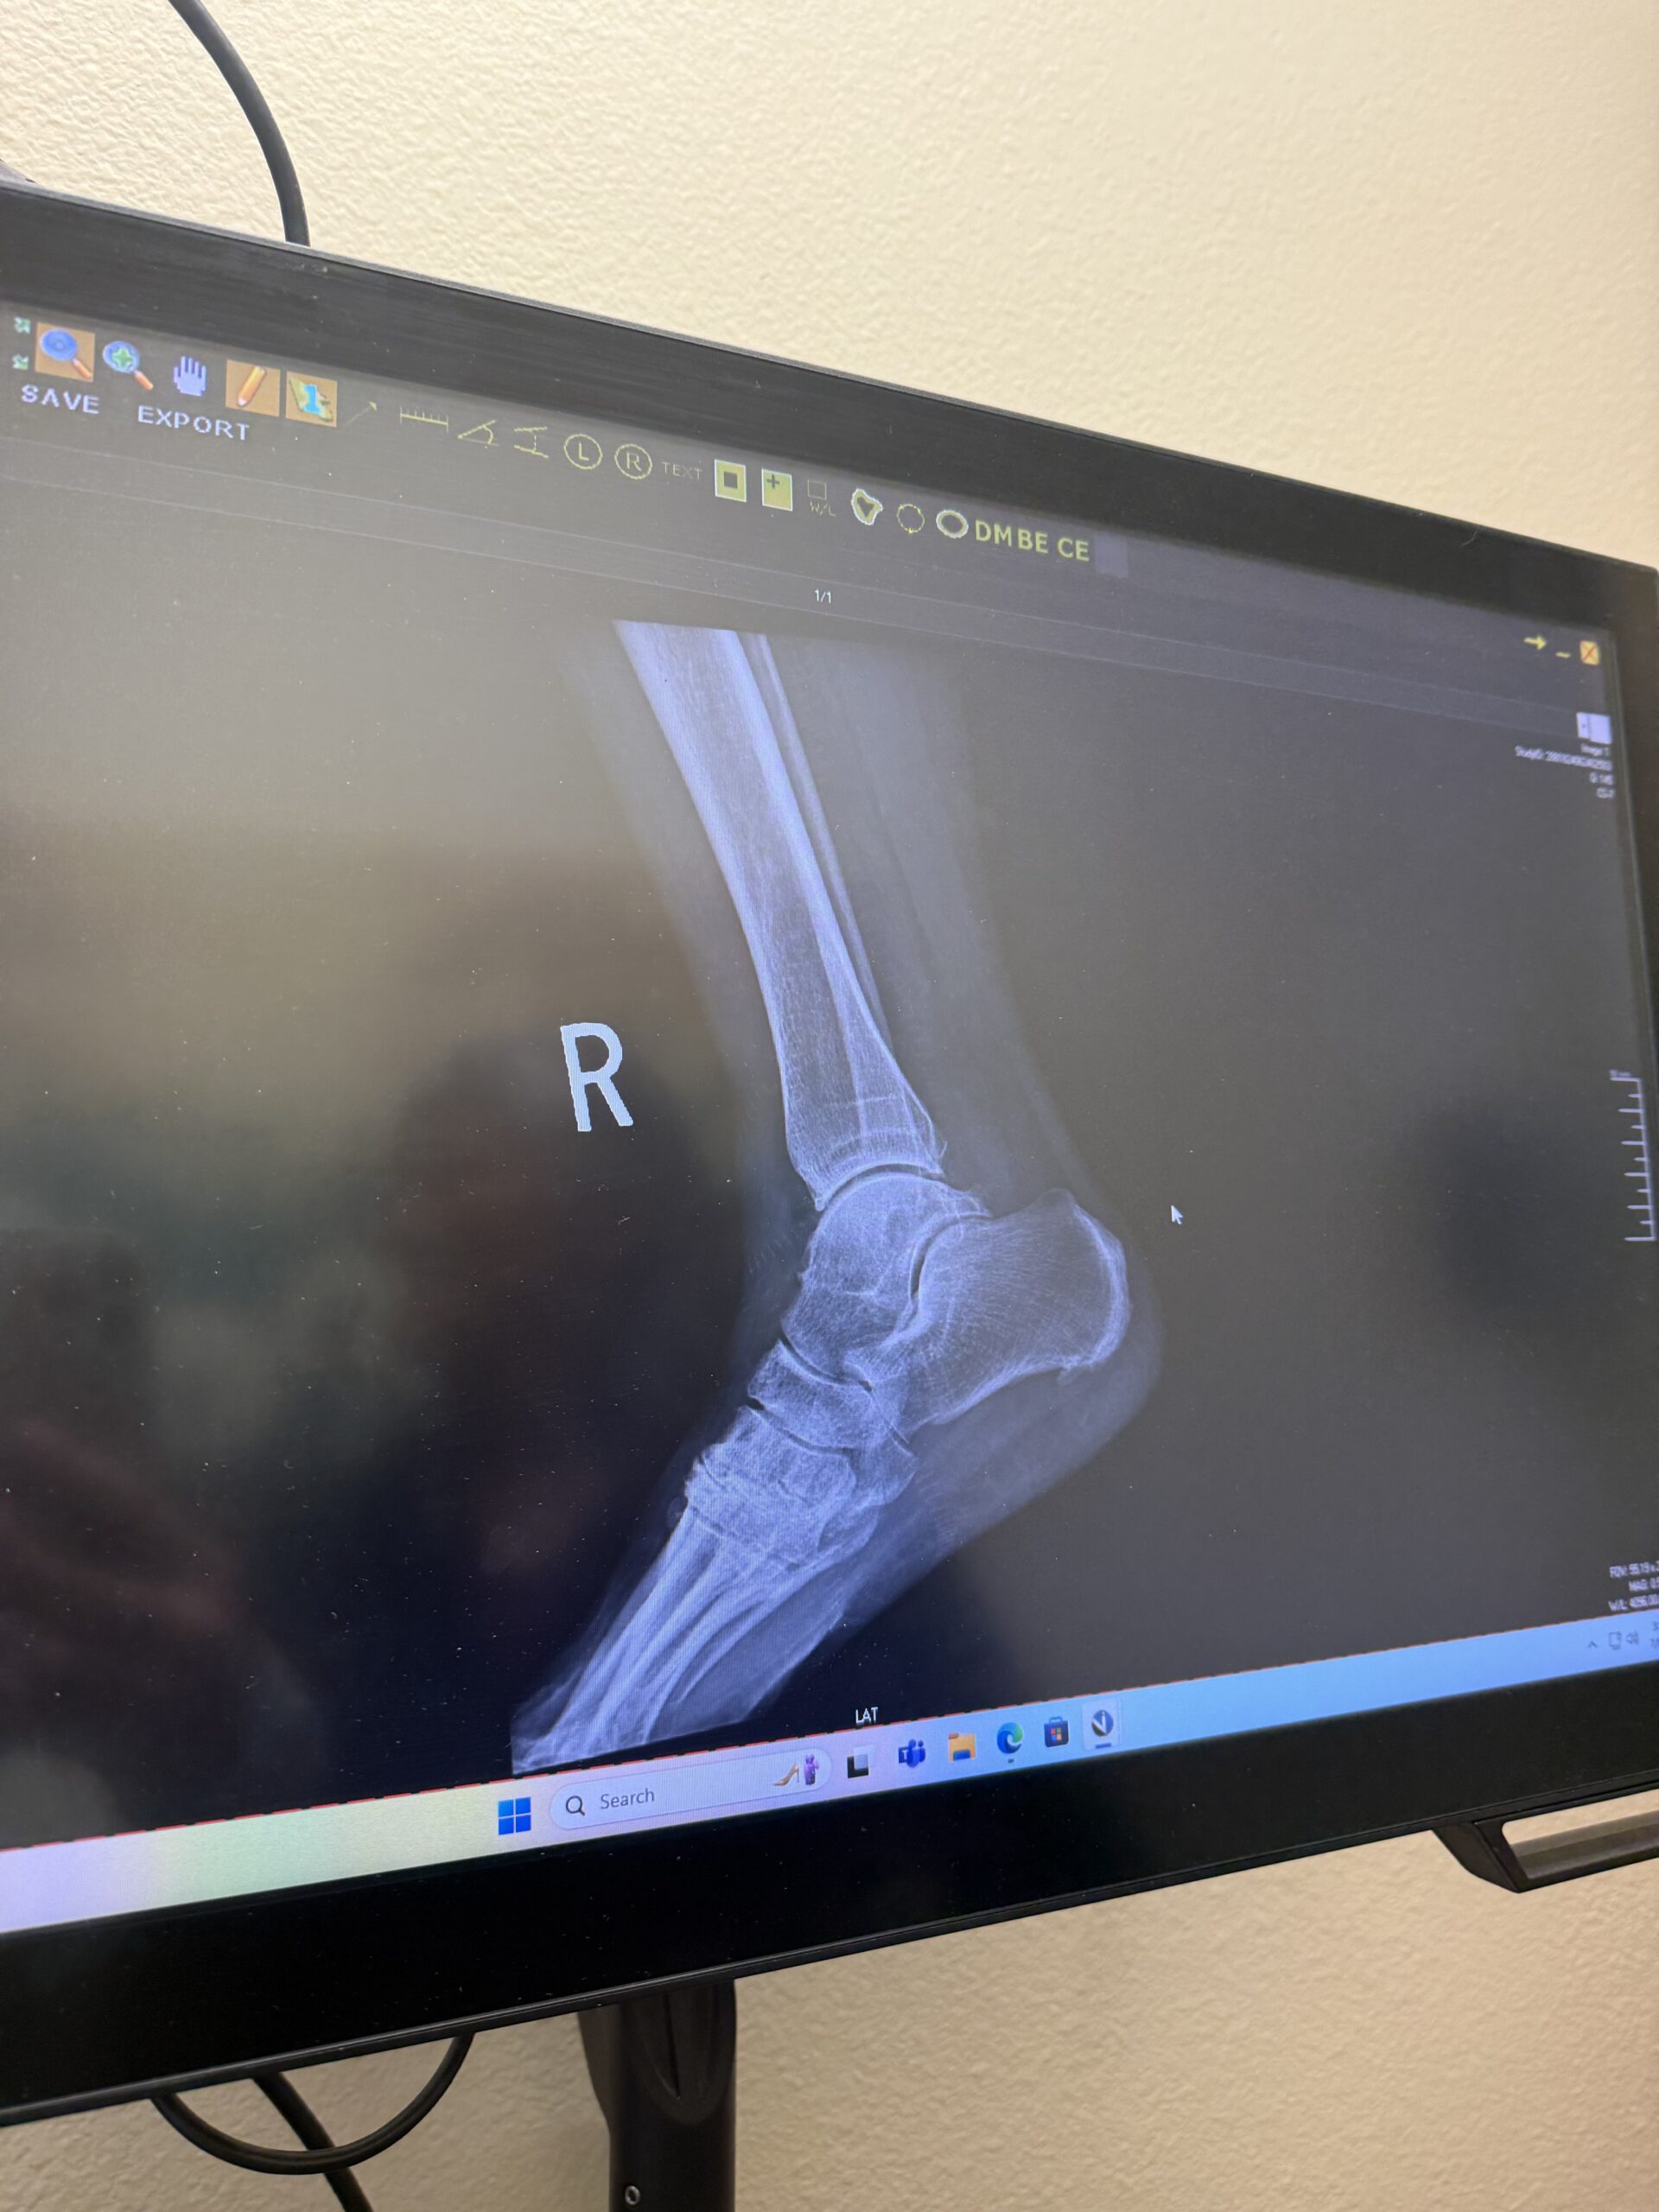

On the last day, I observed some X-rays and learned more about how they’re used to help diagnose patients, which was also really fascinating